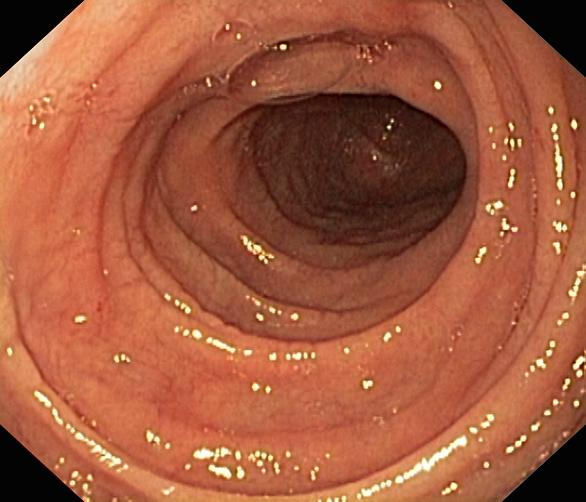

Celiakia